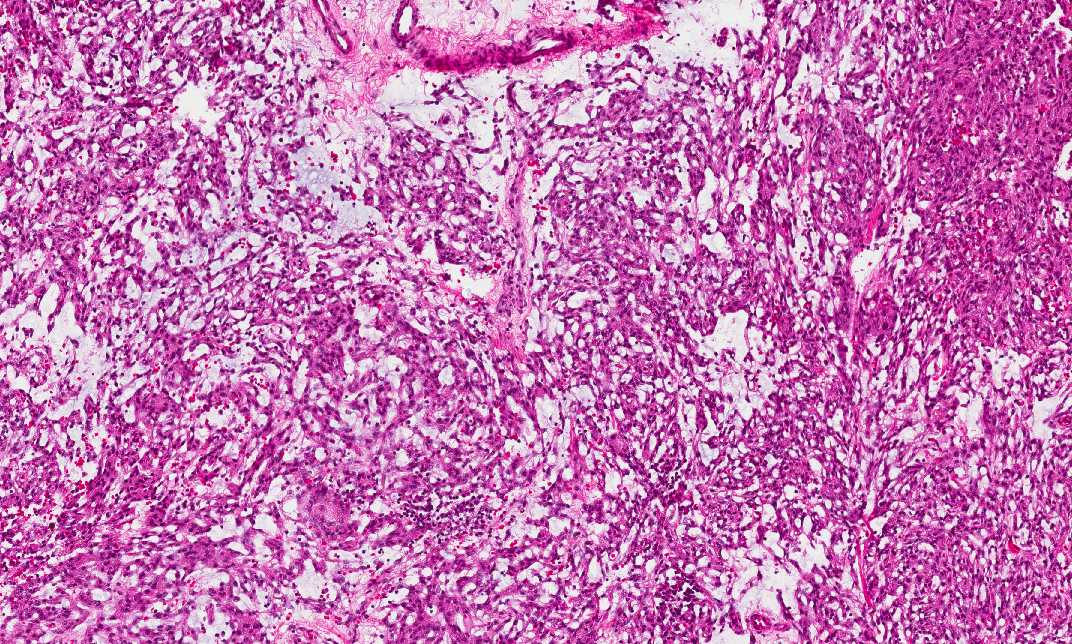

Hematoxylin & eosin

Area 1: The tumor cells are rather spindle in shape and have a vague concentric arrangement. However, classic meningotheliomatous whorls are not present. This type of vague concentric arrangement of tumor cells is a hint for diagnosis in meningiomas. If you pay attention, the cytoplasm of the tumor cells have a fine bubbly type of appearance.

• Certain areas of this tumor is composed of spindle cells that tend to arrange in vague concentric whorls (Area 1). In this areas, there are some small vacuoles in between the tumor cells. Also, the cytoplasm of the tumor cells are vaguely bubbly. However, no significant intercellular substance is noted in between the tumor cells.